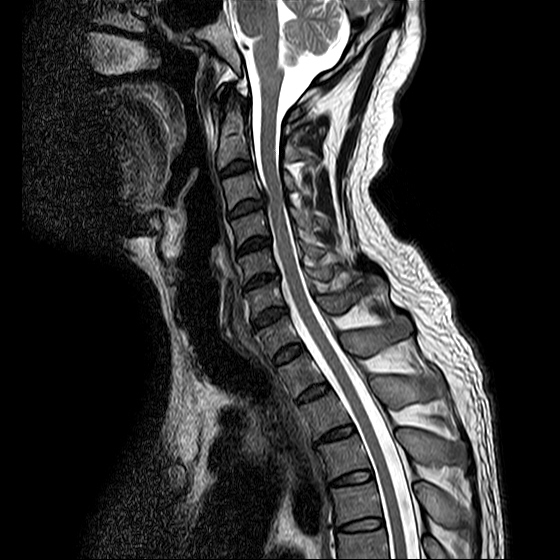

ũ Ͻ е鲲 ǰ ϴ. ڸ 4°Դϴ. ũ ϴ. (ڸǥغ ǥغ ) @ : 2014. 2.15 ĺ Ȳġ Ͽ. -> κ ǿ ġϿ պ ϱ. @ 2014. 3. 27 к mri, ct ũ ϰ ؾ Ѵٰ. @ ũ ġ ͳ Ͽ ڸǥغ Ͽ. ϱ : .(ó ) 2014. 4. 12() --- <1°> : Ͽ ȸ . 㳻 : (ڱ , Ӹ е ħ ˷. ¿ . ų ɰų Ҷ ̰ų ڼ . 201.4. 4. 13() ---<2°> 1. ħ Ͼ ¿ ȭ . 2. ħ е ħ . 3. ü ƮĪ ˷. ڼ ˷ֽŴ ϸ ڼ ùٸ ϸ Ÿ ˷ֽ Ư ƮĪ ϸ Ѱ پ 2014. 4. 14() ---<3°> : : پ(ó ߴ.) 㳻 : 1. ħ Ͼ ¿ ȭ . 2. ũ ˷ . 2014. 4. 14() ---<4°> : پ(ó .) 㳻 : 1. 繫ǿ ũ ٽ 2. ũ ˷ ϸ ڼ ϸ ȸ ̷ ɴ 2~3 ϸ ȸȴٰ Ͻô ū 븦 Ͽ ȸϵ ϰڽϴ. ȸ Ź帳ϴ. ũ mri Ȳ Դϴ. Ű 179 86 51 ()ijħ ڸǥغ ǥغ ˰Ե ͳ ˻ڷ õ ()ijħ ڸǥغ ǥغ ϱ ȣϽ 6C.ڸ 6C.ھ Ḳ 7C.Ȳġ 1T.Ȳġ 1T. κ ()ũ( ߰Ż) ڸ(߹) ũ(߰) Ը ũ(߰Ż)ġ, ()ijħ ڸǥغ ǥغ ϰ ߴ ġ 1. : 2014. 2.15 2. ġ : Ʒ(ô߿ ) , ȱ 3. **뺴 : ˾. Ƽ (ũ ) 4. ó : ڰ, 3 Ⱓ mypol()ó. ȭ. 3 5. ü ġ . |